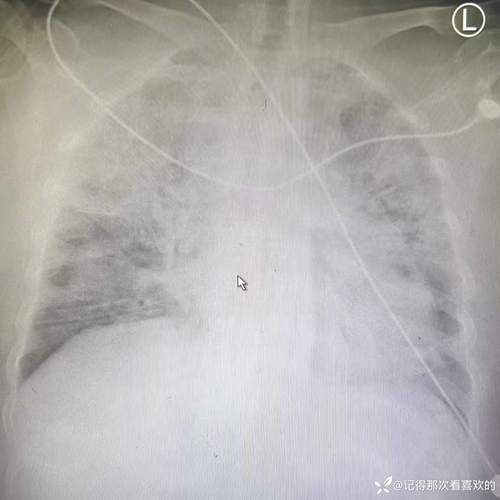

单日新增连续2天突破2万例!新冠重症情况如何?比例明显下降?

〖One〗目前各地本轮疫情中新冠重症比例明显下降,重症及危重症患者数量较少。具体情况如下:广州:自10月22日本轮疫情以来,累计感染者已超3万例,没有重型、危重型患者。北京:1187例感染者中,重型2例,目前所有在院患者病情稳定。重庆:11月以来超8000例感染者中,重型3例。河南郑州:本轮疫情中没有重型和危重型病例。